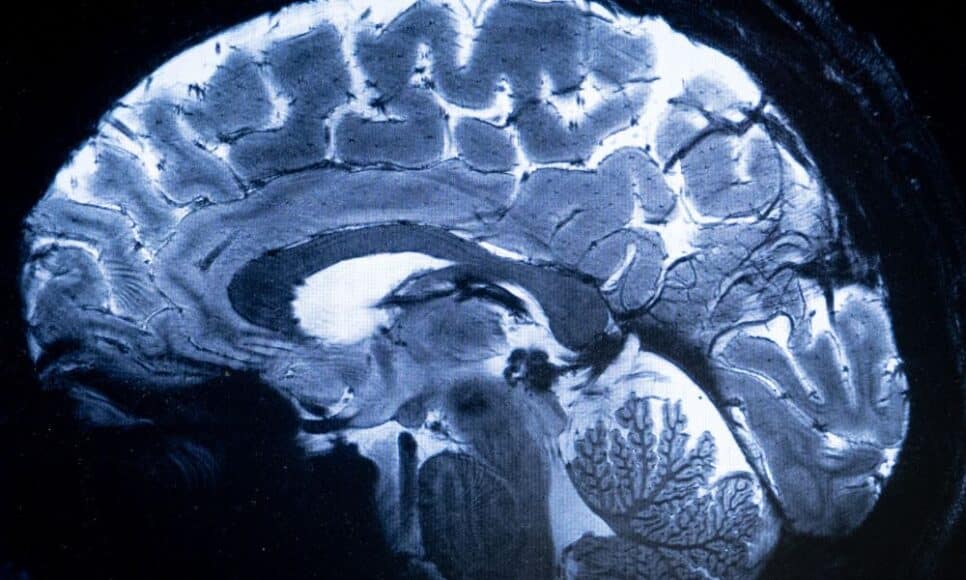

A doença, que impacta de forma irreversível milhões de pessoas em todo o mundo, é atualmente diagnosticada por meio de exames clínicos que demonstram uma perda considerável de memória. Também existem exames por punção lombar ou uma técnica de imagem médica chamada tomografia por emissão de pósitrons (PET-scan), porém estes procedimentos são complexos e dispendiosos. Segundo Jonathan Schott, apenas 2% dos pacientes no Reino Unido se beneficiam desses dois exames. Um exame de sangue seria “muito mais acessível e menos caro”, destaca o professor.

Fiona Carragher, diretora de pesquisa da Alzheimer’s Society, lamenta que a demência seja frequentemente diagnosticada tardiamente, o que restringe o acesso a intervenções, tratamentos e a capacidade de planejar o futuro. A doença de Alzheimer se desenvolve através da formação de placas de proteínas chamadas amiloides no cérebro, que comprimem os neurônios e acabam destruindo-os, ou devido ao acúmulo de outras proteínas, chamadas Tau, dentro dos próprios neurônios.

O exame de sangue mais recente possibilita a medição de um marcador denominado p-tau217, que indica a existência das duas proteínas, e será utilizado em conjunto com os testes cognitivos. Se o estudo clínico for bem-sucedido, o exame de sangue poderá ser um componente-chave no diagnóstico da doença de Alzheimer.